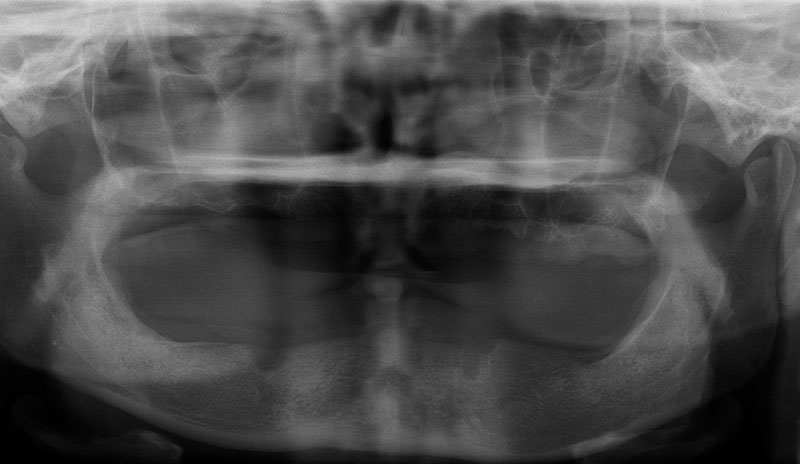

植牙的目的,就是將原來已經失去的咬合能力復原,因此必須更謹慎的評估患者骨質的密度、高度和寬度是否都能滿足植牙的條件。

許多人缺牙多年後才想要植牙,但此時齒槽骨已萎縮,少了堅固的骨頭做為牙根的支撐當然不會穩固。因此可以把補骨想成幫牙根打地基,有了堅硬的地基再植入人工牙根,植牙效果才會穩定耐用。